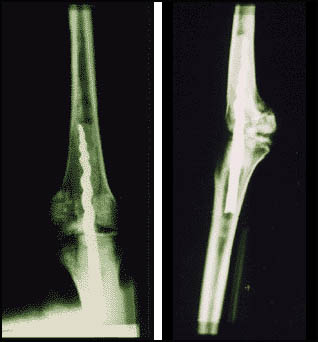

In August 1995, Dr. Wilfred Griggs led a team of scientists from Brigham Young University who were conducting DNA research on the six resident mummies in the Museum . During the research, an X-ray revealed a metal pin in the left leg of Usermontu. At first Dr. Griggs thought the screw "must have been a recent attempt to repair the mummy, maybe no more than 100 years ago. When we first saw the x-rays in August, I thought it was interesting that some modern person would go to this much trouble to fix the leg, because I've never known or seen something like it. It never occurred to me at that time that there could have been anything ancient to this." continued Griggs.

So intrigued by the possibilities of this find, that in November Dr. Griggs returned to the Museum one evening to take a closer look. After about 30 minutes of looking closely at the leg, Dr. Griggs decided that the pin was much older than he anticipated, and was so excited that it was worth a full scale investigation.

On February 8, 1996, Dr. Griggs returned with specialists to determine if this was the first attempt at ancient knee surgery ever discovered. And to our surprise, there is no doubt in anyone's mind that this is definitely an ancient operation. Never before has an Egyptian mummy anywhere exhibited such a characteristic.

Dr. Griggs and his retinue of researchers from Brigham Young University were themselves taken aback at the historical implications of this metal pin. Throughout the day-long procedure, initial findings elicited provocative questions as to the exact function and nature of the pin. Was the pin inserted while he was still living or just after he died? Was the pin placed in the knee as a result of some sort of trauma?

To date, we know that the metallic composition of the corkscrew pin consists of pure iron, and that it was put in before Usermontu was mummified. This corresponds with the accepted time period of Usermontu's life (ca. 630 B.C.) and Egypt's iron age.

In addition to the drilling done, researchers were able to insert a small probe to look inside the leg and get a glimpse of the pin, as well as see a glue-like resin surrounding it, probably used to cement the screw into place.

Not only were the researchers amazed that the pin is ancient, but the highly advanced design had the visiting surgeons in awe.

"The pin is made with some of the same designs we use today to get good stabilization of the bone," said Dr. Richard Jackson, an orthopedic surgeon from BYU.

Apparently, the ancients knew how to use the flanges on a screw to stabilize the rotation of the leg.